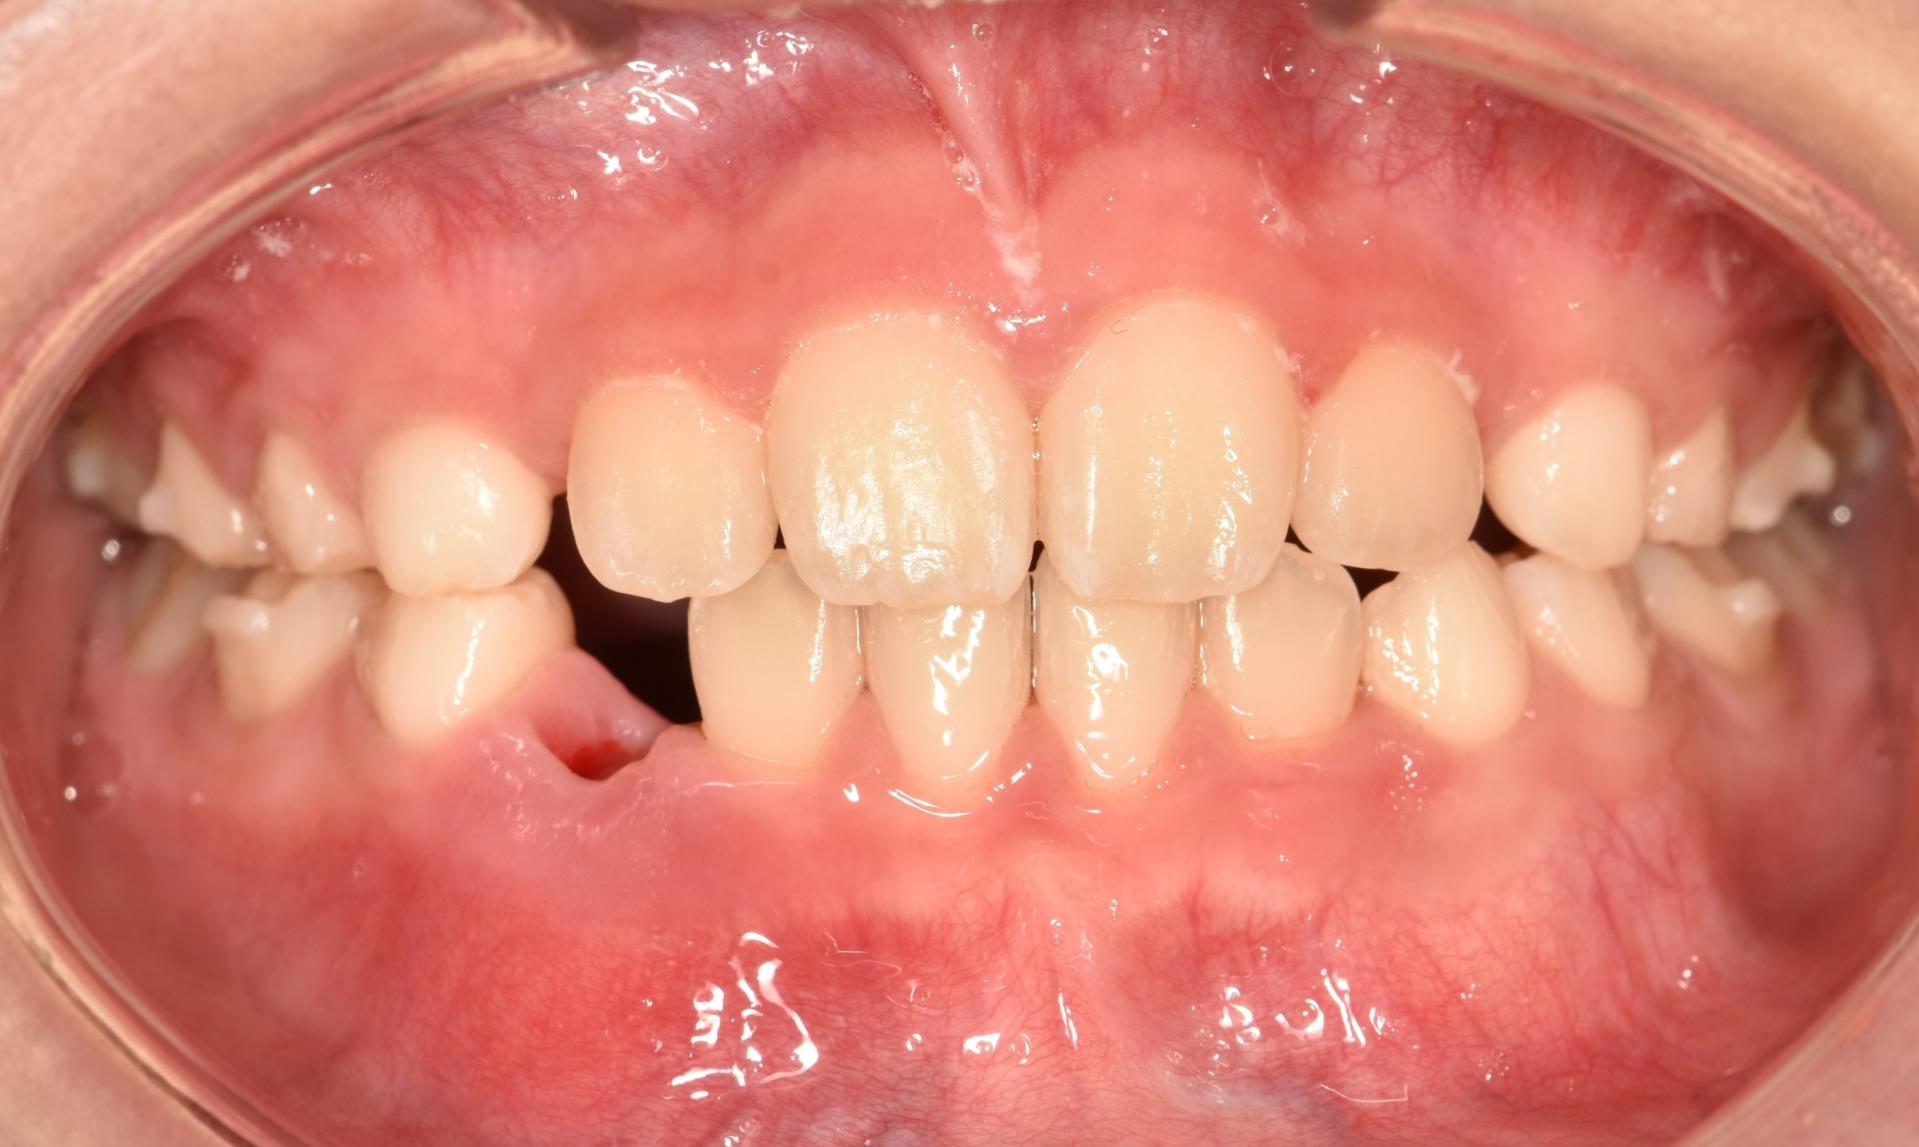

1년의 교정치료 기간 끝에 뻐드러진 치아도 안으로 예쁘게 넣었고 부딪히는 치아 없이 배열도 완료 되었습니다. 더불어 덧니되지 않도록 앞으로 나올 송곳니의 자리까지 마련했답니다.